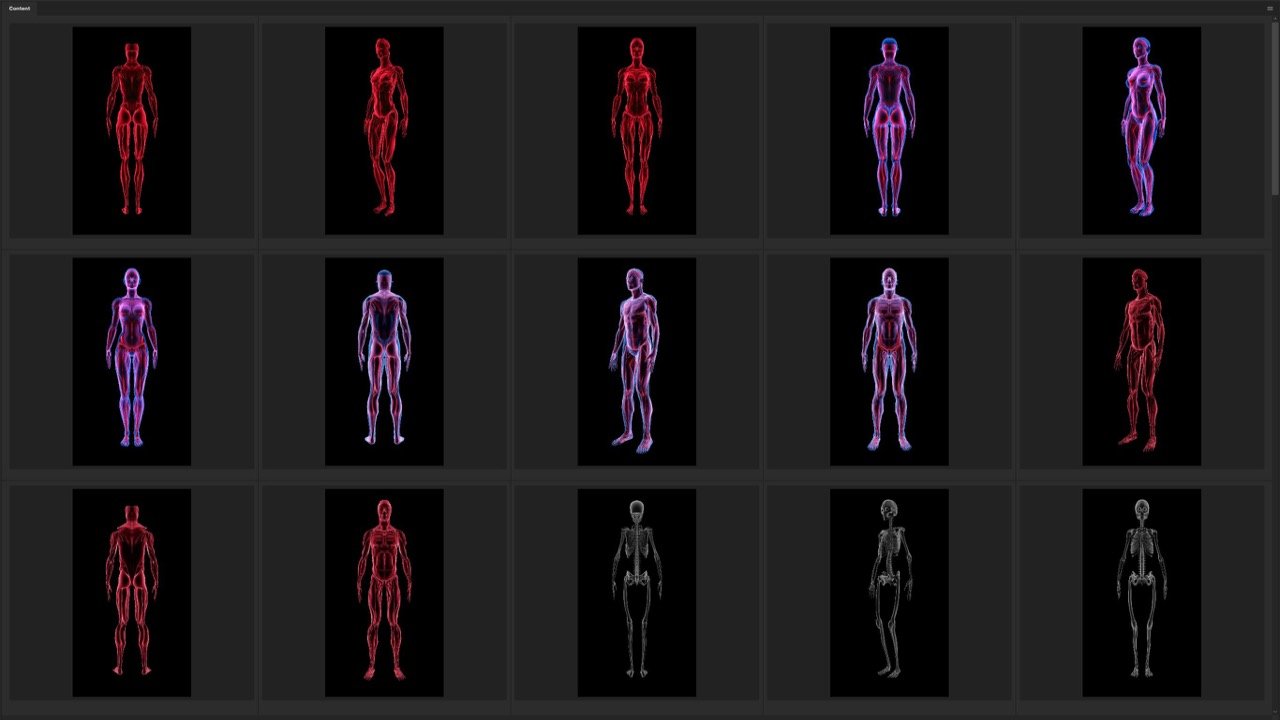

Versatility and Variety

Our Stock-Packs™ are curated to include a varied

range of angles, motion, styles and formats,

ensuring that creators can find the assets

they want fast and easy.